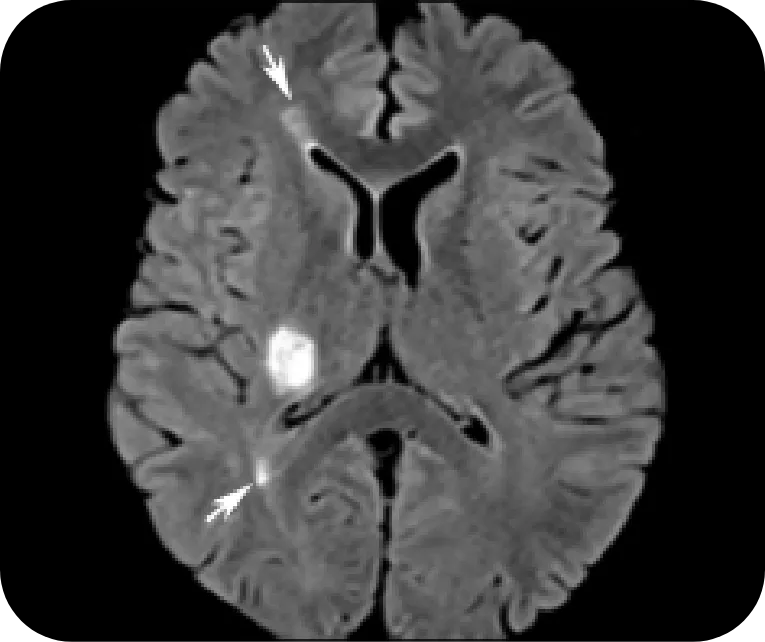

Brain

NMOSD

Ovoid and longitudinally short lesions typical of MS myelitis

Reprinted with permission from Radiographics, 2018;38(1):169-193. ©RSNA

MS

Focal acute lesion in the right posterior limb of the internal capsule. Lesions are concomitantly observed in the periventricular white matter (arrows)